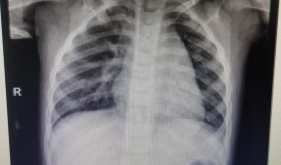

中山博爱医院儿童重症加强监护病房(PICU)成立于2001年,是广东省临床重点专科重要分支、中山市十三五高水平临床重点专科、珠三角重症手足口病指定救治点之一、中山市儿童重症救治中心,是中山市儿童新型冠状病毒医疗救治专业组组长单位。现有专业医师8名,其中主任医师2名,副主任医师1名,护理人员25名,专科护士数名。年收治患儿1000余人次。拥有国内先进的硬件设施,可满足各类外科监护、重大创伤救治和多器官功能衰竭救治。配置吊塔(1...